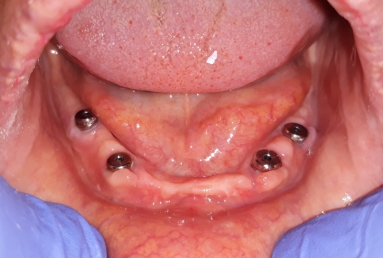

Mobile Prosthesis fixed with 4 locators on 4 Alpha BIO Nobel dental implants

Mobile Prosthesis fixed with 4 locators on 4 Alpha BIO Nobel dental implants.

Female patient with advanced periodontal disease has mobility of all teeth and old dental work. All mandibular teeth were extracted and replaced with 4 dental implants ( Alpha bio Nobel).